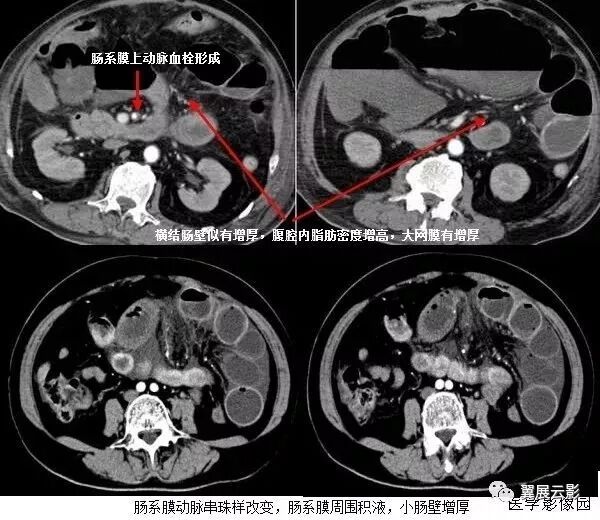

5、肠系膜混浊征

肠系膜脂肪受炎症细胞、液体(水肿、淋巴液和血液)、肿瘤浸润及纤维化的CT表现。当肠系膜被液体或细胞浸润时,其脂肪CT值增加到-40~ -60HU(肠系膜脂肪的CT值类似于皮下及腹膜后脂肪,约-100~-160hu,肠系膜血管常呈横行或断面显示。),动、静脉失去锐利边缘。根据浸润的性质和范围,肠系膜血管可部分或完全模糊,顺着脏层腹膜常能发现肠系膜疾病的线索,在周围脂肪衬托下,肠系膜病变显示更加清晰。

上两幅图:肠系膜上动脉栓塞

下两幅图:十二指肠扭转致肠壁增厚、肠系膜水肿

(1)肠系膜水肿

肠系膜水可由许多疾病引起,如低蛋白血症、肝硬化、肾病、心力衰竭、三尖瓣狭窄病变、缩窄性心包炎、门脉高压、门静脉血栓、肠系膜血管栓塞、血管炎、柏-查综合征、下腔静脉阻塞和外伤等,如肠系膜水肿是由全身性疾病引起,则有广泛的皮下水肿和覆水。CT扫描常由于身体近床侧的皮下组织内有新月状高密度影,代表增多的细胞外水分,肠系膜呈云雾状改变的范围从肠管的浆膜面直到肠系膜上动、静脉起始部的肠系膜根部;肝硬化由于低蛋白血症门脉高压常引起肠系膜水肿。肠系膜动、静脉血栓所引起的肠系膜水肿可呈局限性或弥漫性,发现血管内栓子或管腔缩小常可提示肠系膜血管栓塞,肠缺血的其他征象为节段性肠壁增厚,气肿性肠炎,当出现坏死时可有小静脉分支内集气。